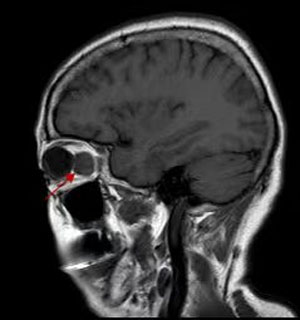

B超、CT、核磁共振等影像學檢查都必不可少,可以提供病變的位置、大小。細針穿刺活檢創傷小,但可以獲取細胞學標本,幫助診斷。有的病例需要手術活檢進行病理檢查明確診斷,指導治療。

就腫瘤而言,手術完整摘除是最常用的治療手段,由于在眼眶有限的空間內,集中了眼球、視神經、眼外肌、供養血管等重要結構,因此手術是有難度的。醫生根據眼眶腫瘤的位置選擇最佳的手術路徑,借助于先進的頭戴放大鏡系統,使手術操作更加準確,最大程度減少了并發癥。